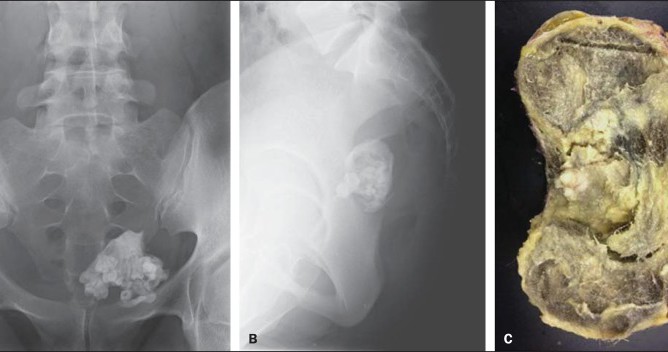

В 2015 году в Бразилии 25-летняя женщина обратилась к врачу с жалобами на боль в нижней части спины, мучившую ее уже два месяца. Первичный осмотр не выявил никаких патологий, в вот УЗИ органов таза показало крупное, 10,3×9,2×8,6 см, образование в области яичника.

После удаления врачи установили, что оно состояло в основном из жировой ткани, но также в опухоли содержались волосы и зубы.

Зубы — не редкость для тератом яичника, они обнаруживаются более чем в трети случаев. Периодически они попадаются даже в археологических находках — так, фрагменты новообразования были найдены среди тазовых костей женщины древнеримской эпохи в Испании. В небольшом шарике среди тазовых костей древней римлянки оказались четыре зуба и кусок кости.